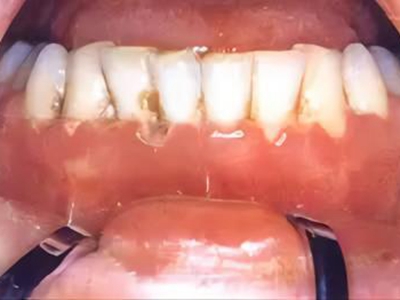

急性坏死性溃疡性龈炎起病急,病程短,常为数天至1-2周,以龈乳头和龈缘的坏死为其特征性损害,尤以下前牙多见,初起时龈乳头充血水肿,个别龈乳头顶端可发生坏死性溃疡,上覆有灰白色坏死物,中央凹下如火山口状。龈缘如虫蚀状,坏死区出现灰褐色假膜,擦去后可见出血创面。龈乳头被破坏后与龈缘成一直线,如刀切状。病损一般不波及附着龈,患处牙龈极易出血,疼痛明显并有腐败性口臭。